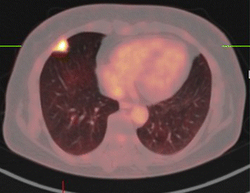

PET/CT — Pulmonary Tuberculoma

Combined PET/CT scan showing FDG-avid pulmonary tuberculoma in the chest

PET Downloaded 2026-03-15

Pet

Fdg

Wikimedia Commons: PET-CT of a tuberculoma.png